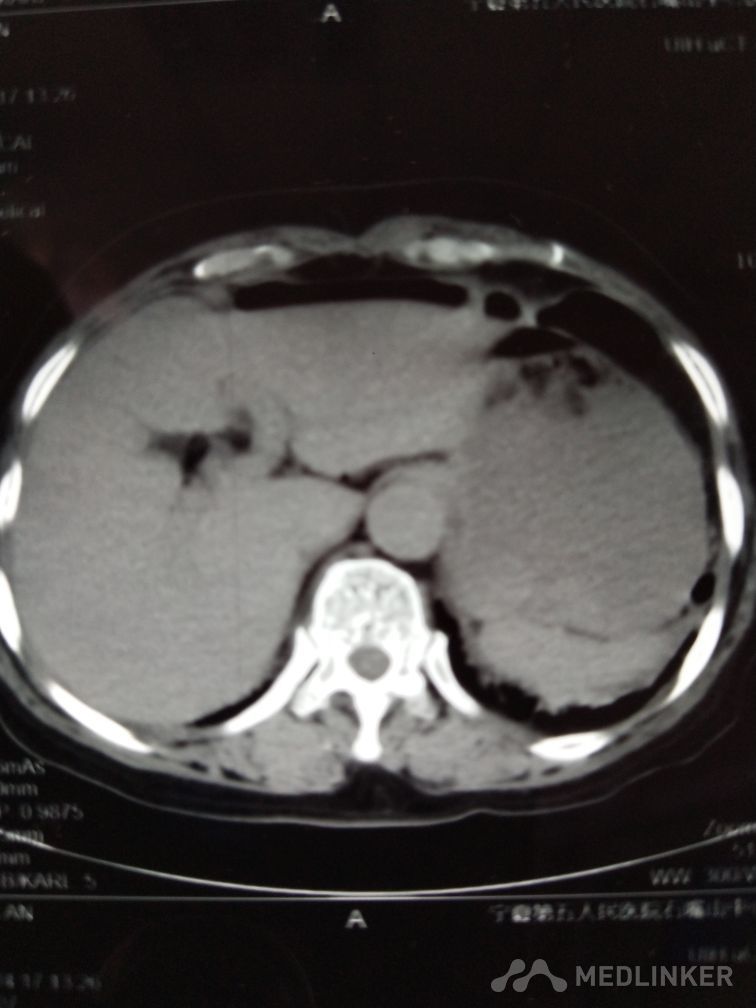

胃穿孔